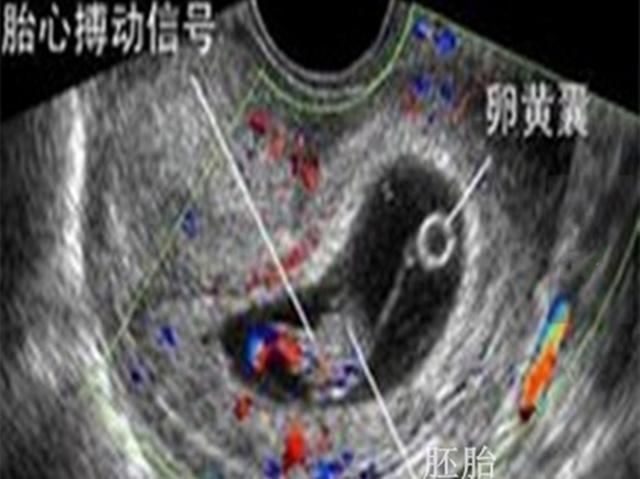

第二项,透过B超看胎儿,B超是目前使用最广泛的胎儿影像学监护仪器,可以观察胎儿大小,胎动,羊水情况,胎儿畸形筛查等。